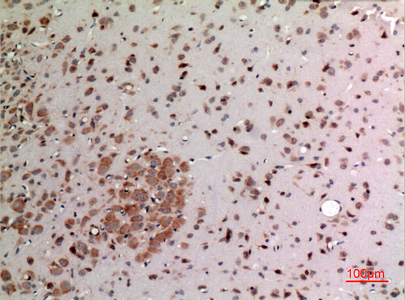

- Immunohistochemistry analysis of paraffin-embedded rat brain using FGF20 antibody.High-pressure and temperature Sodium Citrate pH 6.0 was used for antigen retrieval.

- Immunohistochemistry analysis of paraffin-embedded rat brain using FGF20 antibody. High-pressure and temperature Sodium Citrate pH 6.0 was used for antigen retrieval.